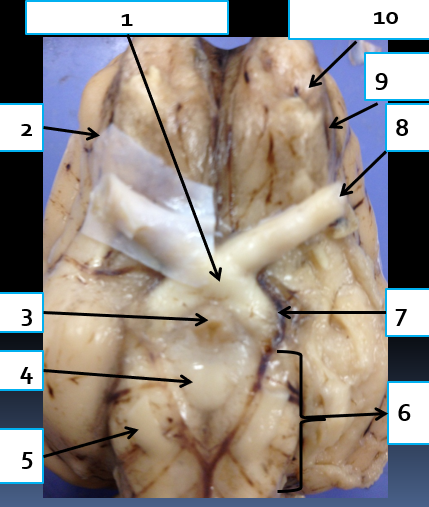

1

optic chiasma, area where medial portion of optic nerves cross

2

dura mater, protects brain

3

infundibulum, connects hypothalamus to pituitary gland

4

mammillary body, relay station for olfaction

5

oculomoter nerve, CN3, eye muscle control

6

cerebral peduncle, connects cerebrum to pons

7

optic tract, carries visual information from optic chiasma to visual cortex

8

optic nerve, CN2, vision

9

olfactory tract, carries impulses associated with sense of smell to the brain

10

olfactory bulb, houses synapses of olfactory nerve fibers, CN1, olfaction